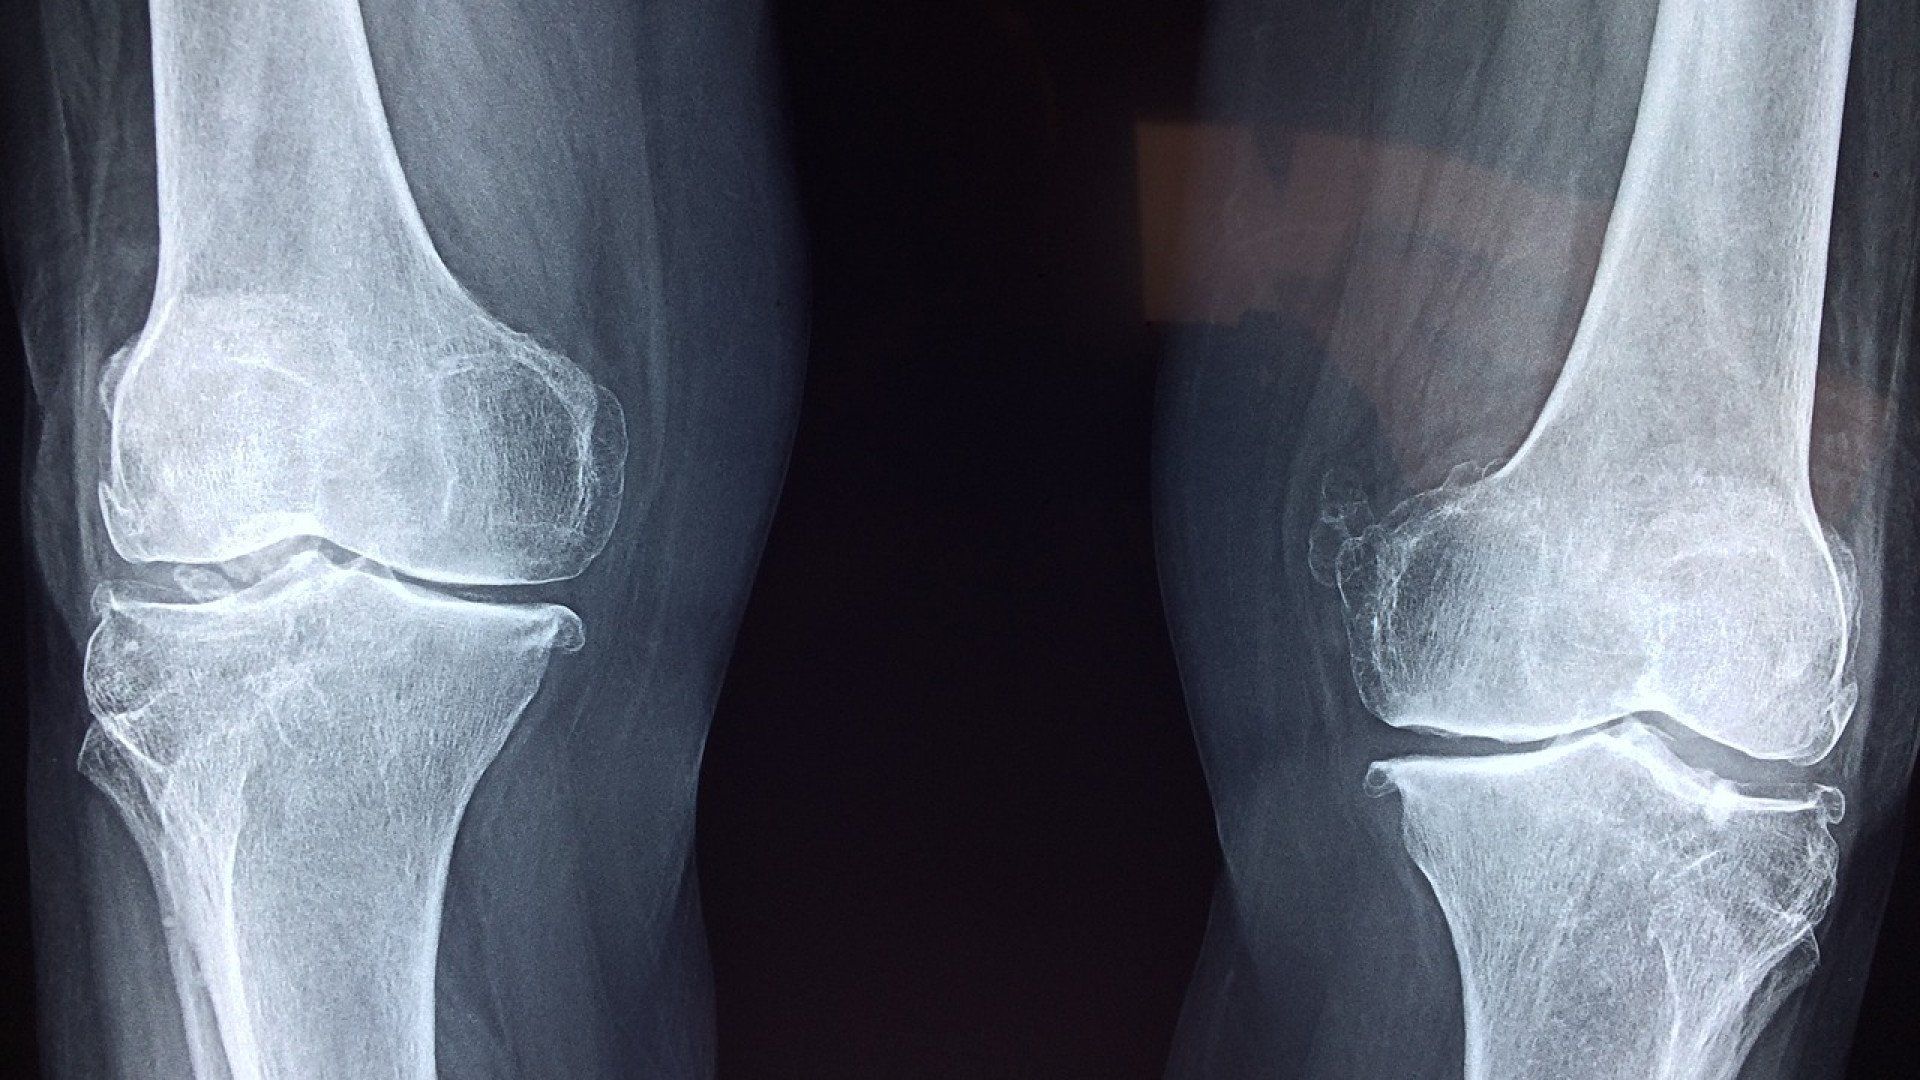

LES INJECTIONS DE PRP POUR L'ARTHROSE

Effet des PRP sur l'arthrose du genou grade I-II.